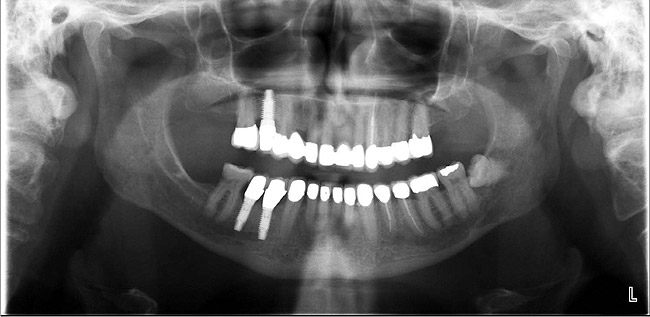

Figure 10c  Traditional fixed prosthodontics performed to level the opposing arch and regain sufficient crown height space.

Figure 10c

Figure 10d  Traditional fixed prosthodontics performed to level the opposing arch and regain sufficient crown height space.

Figure 10d